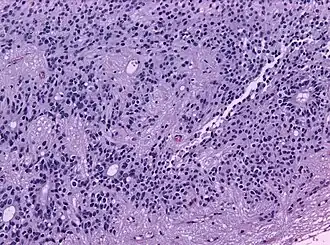

Псевдорозетки Гомера Райта является одним из видов псевдорозеток, в котором дифференцированные клетки опухолей окружают нейропиль.[7] Примерами опухолей, содержащих эти розетки, являются нейробластома, медуллобластома, пинеалобластома и примитивные нейроэктодермальные опухоли кости. Розетки Гомера Райта являются «псевдо» в том смысле, что они не настоящие розетки. Настоящие розетки — это розетки Флекснера-Винтерштайнера, которые содержат пустой просвет. Розетки Гомера-Райта содержат большое количество фибриллярного материала. Они названы в честь Джеймса Гомера Райта.

Микроскопический вид типичной нейробластомы с образованием розеток